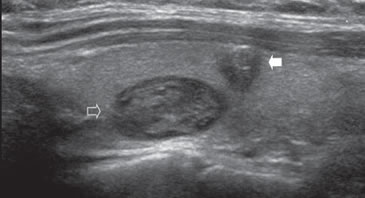

7. Invasión local y adenopatías

La extensión de la masa fuera de la cápsula, la infiltración de la tráquea o de los músculos pretiroideos es muy sugerente de malignidad (Figura 15a). Asímismo, la presencia de adenopatías con características típicas, debe hacer sospechar que el nódulo tiroideo es maligno. Los cánceres papilares de la tiroides son propensos a dar metástasis precozmente a los linfonodos cervicales y hasta la mitad de todos los pacientes pueden presentar adenopatías concomitantes. En 15% de los pacientes, el único signo de un cáncer tiroideo papilar oculto puede ser la detección de adenopatías. La mayoría de las metástasis ocurren ipsilateralmente al tumor primario en los grupos III y IV de la cadena yugular interna y del grupo VI del compartimiento central. En la ecografía, los linfonodos metastáticos pueden tener una forma redondeada o globular, una arquitectura con elementos sólidos o quísticos, con o sin microcalcificaciones y pérdida del hilio (Figura 15b y c). El “Doppler color” puede demostrar vasos capsulares de distribución caótica en reemplazo de los vasos hiliares normales (Figura 15d). Las adenopatías hiperecogénicas son sospechosas de cáncer papilar (Figura 16a). Los linfonodos normales en algunos grupos como el VI y el VII no se ven ecograficamente, de manera que si se hacen visibles, en el mismo lado del tumor, independiente del tamaño que tengan hay que considerarlos como adenopatías metastásicas (Figura 16b)

Figura 15. a) Cáncer papilar sólido de bordes lobulados (flechas) que muestra una gruesa calcificación central (flecha abierta) y múltiples

microcalcificaciones; b) Adenopatía cervical del grupo IV del mismo paciente (figura 15 a), hiperecogénica, con elementos quísticos (flecha

blanca) y microcalcificaciones agrupadas (flechas negras), típica de cáncer papilar; c) Adenopatías de grupo IV de un cáncer papilar, de

forma redondeada, hiperecogénicas, con pérdida del hilio, una anterior a la arteria carótida común (flecha) y otra lateral a la vena yugular

interna (flecha abierta); d) Corte sagital de la adenopatía lateral de la imagen 15 c), que en “doppler color” muestra vascularización patológica

y pérdida del hilio.

La apariencia ecográfica de los linfonodos metastásicos puede ser distinta a las del tumor primario y mostrar elementos quísticos y microcalcificaciones en mayor proporción que en el primario. En pacientes más jóvenes, las adenopatías puramente quísticas son relativamente comunes y cuando son solitarias pueden simular un quiste branquial o un quiste del conducto tirogloso.